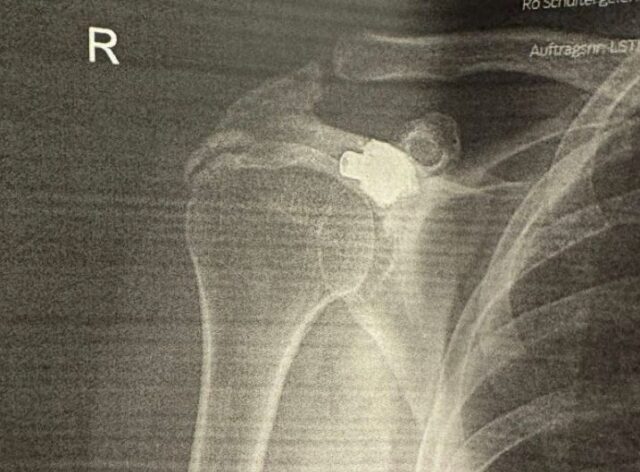

Pas analizave dhe fotografimeve, mjekët konstatuan diçka të jashtëzakonshme. Në krahun e djathtë të tij ndodhej plumbi i marrë 27 vjet më parë.

Sipas tyre, plumbi kishte depërtuar nga krahu i majtë në të djathtin, pa prekur asnjë organ vital, duke qëndruar i fshehur në trupin e tij për më shumë se dy dekada.